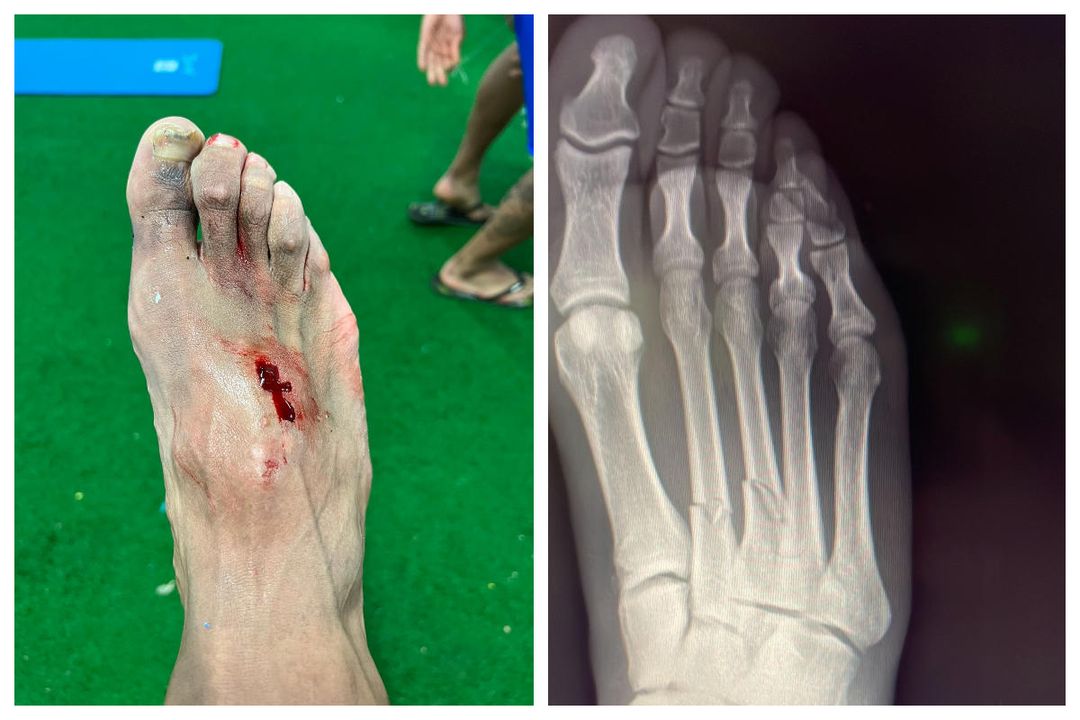

Así quedó el pie de Akapo tras la dura entrada de Hazard y por la que estará de baja dos meses

Imágenes colgadas por Carlos Akapo sobre el estado de su pieJesús Mejías

Posteriormente, ya en el vestuario, Carlos Akapo colgaba una foto en sus redes sociales en la que mostraba cómo había quedado su pie tras la durísima entrada por parte del futbolista del Real Madrid que incluso le hizo sangrar. Además, el futbolista ironizaba con el color de la tarjeta que había enseñado Mateu Lahoz a Hazard debido a la dureza de la acción que lesionaba al lateral.

El propio Carlos Akapo informaba que tiene el segundo y el tercer metatarsiano roto y agradecía todo el apoyo recibido en las últimas horas.

El club ha lanzado un comunicado en el que ha señalado que la estimación de baja para el jugador son ocho semanas, por lo que no podrá jugar a fútbol en dos meses.